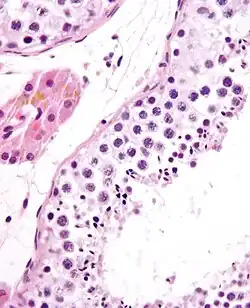

Seminiferous tubule (transverse section).

Photomicrograph of section through rat testis, showing seminiferous tubules.

The epithelium of the tubule consists of a type of sustentacular cells known as Sertoli cells, which are tall, columnar type cells that line the tubule.

In between the Sertoli cells are spermatogenic cells, which differentiate through meiosis to sperm cells. Sertoli cells function to nourish the developing sperm cells. They secrete androgen-binding protein, a binding protein which increases the concentration of testosterone.